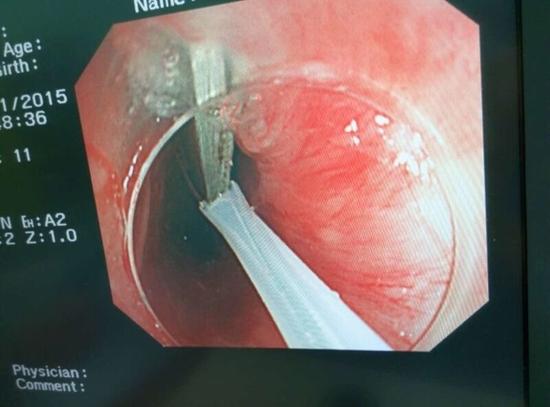

醫(yī)生從華先生胃里取出的鑷子和打火機

隨后,范醫(yī)生先用圈套器套取出了長10厘米的鑷子,再一個一個地取出了打火機。整個取出過程小心謹(jǐn)慎而又一氣呵成,只用了不到10分鐘。